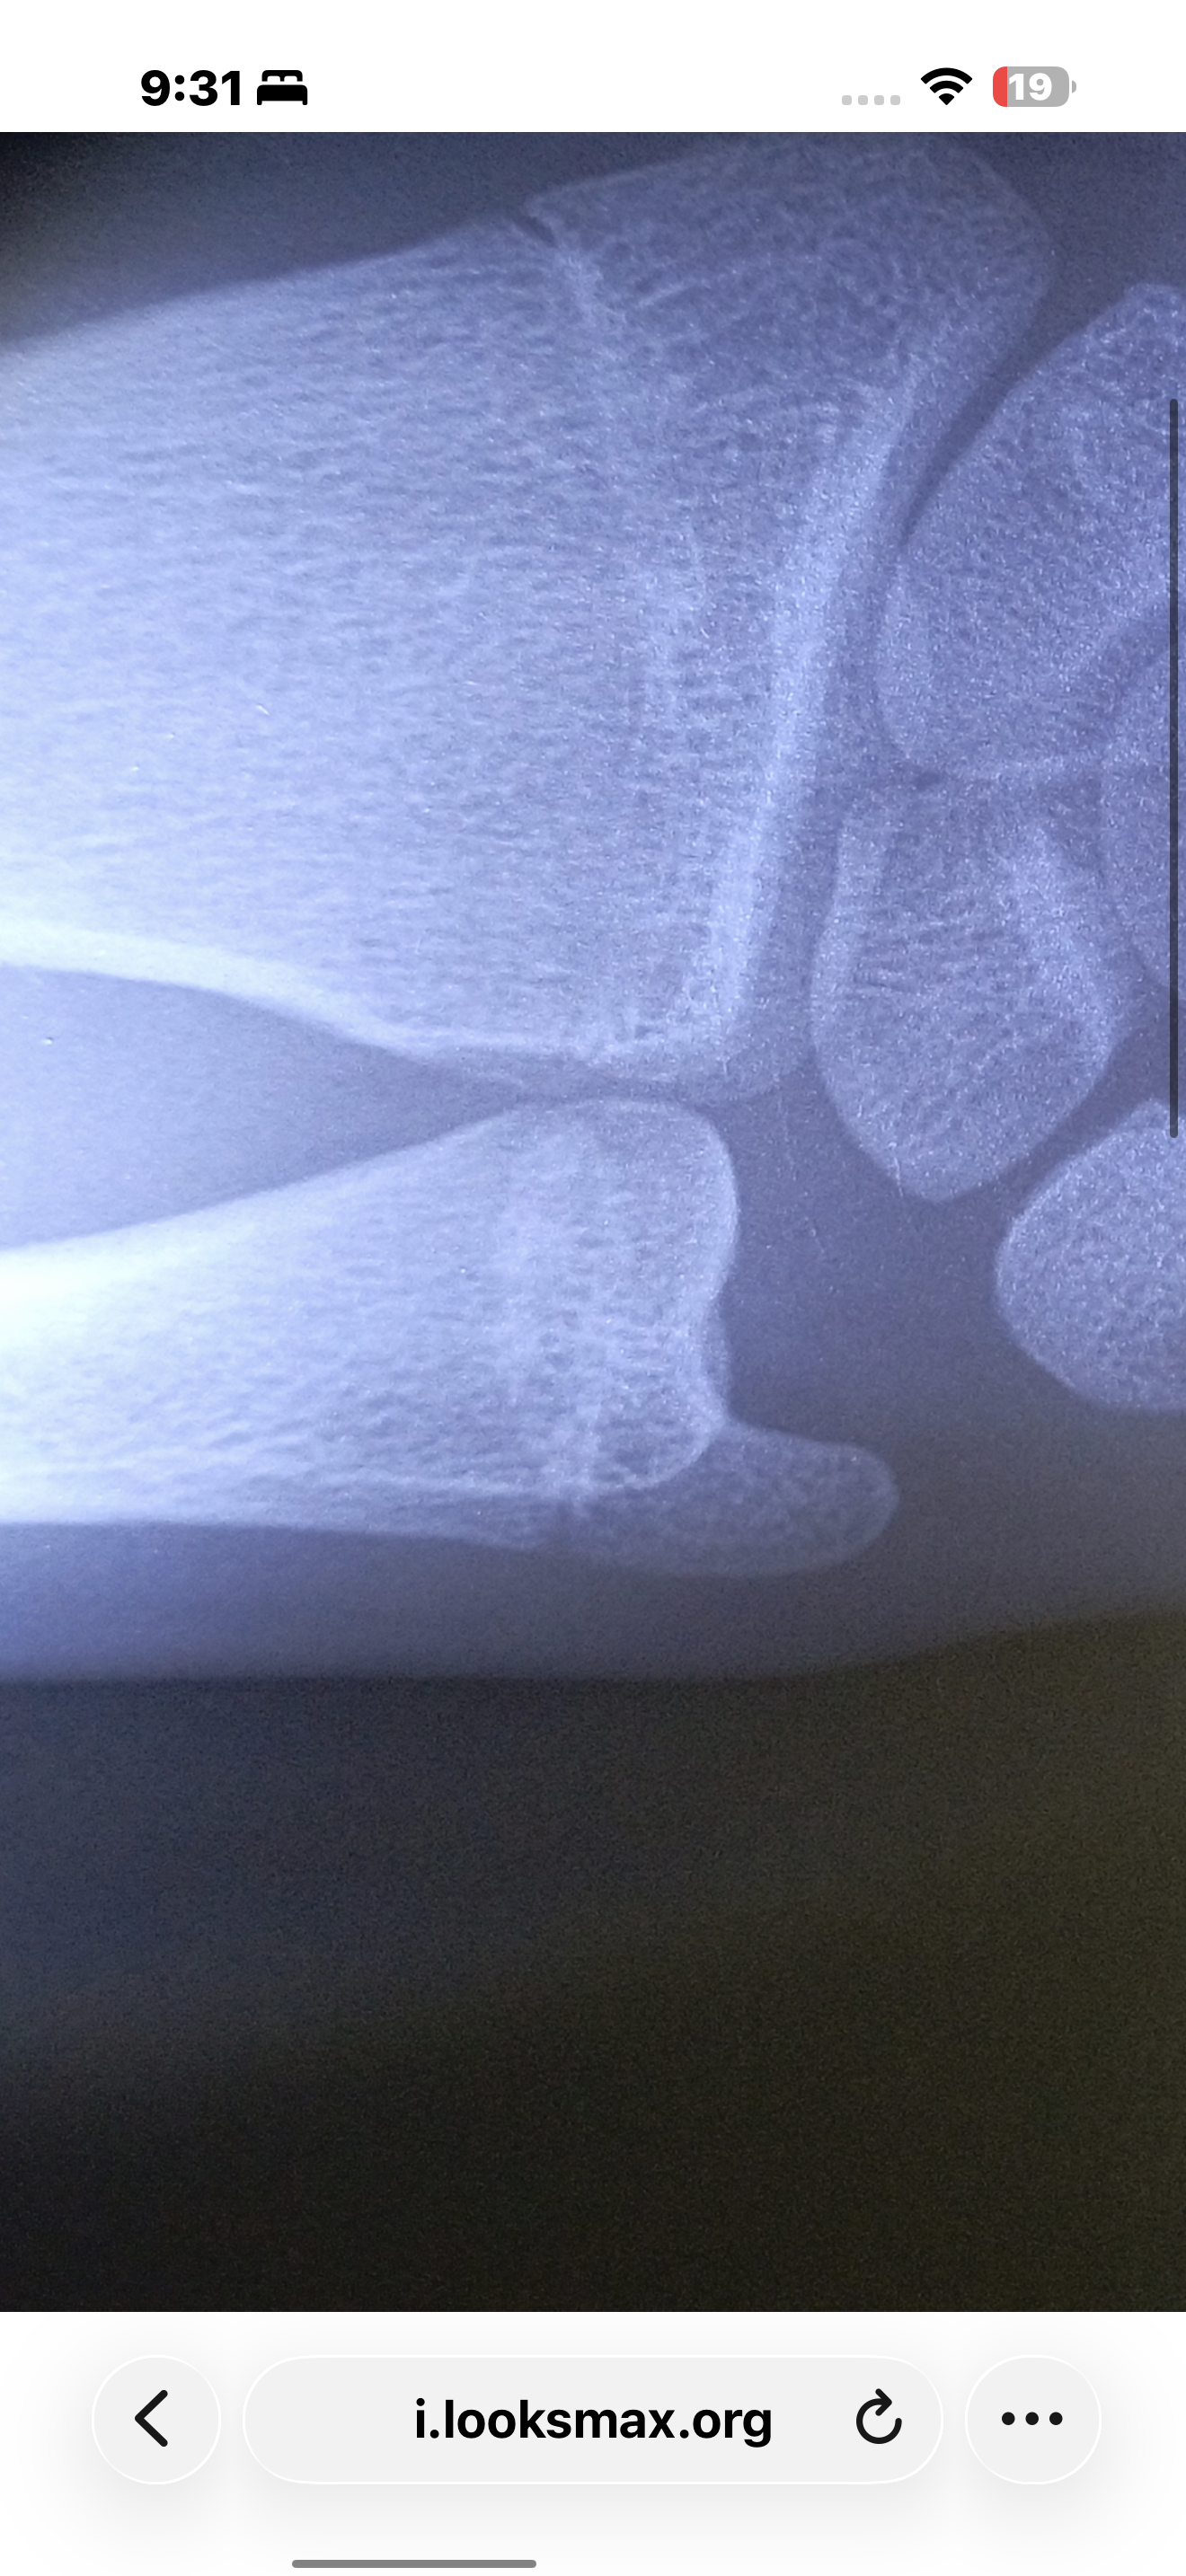

What u thikI don't think so![]()

Bro u'r 14 and they look just as mine even tho I'm 18 how is ts possibleWhat u thik

Yeah yours is more open than mineBro u'r 14 and they look just as mine even tho I'm 18 how is ts possible

No bruh they don’t look alikeBro u'r 14 and they look just as mine even tho I'm 18 how is ts possible

How much height u gained or got told by docYeah yours is more open than mine

Mines visibly more opened